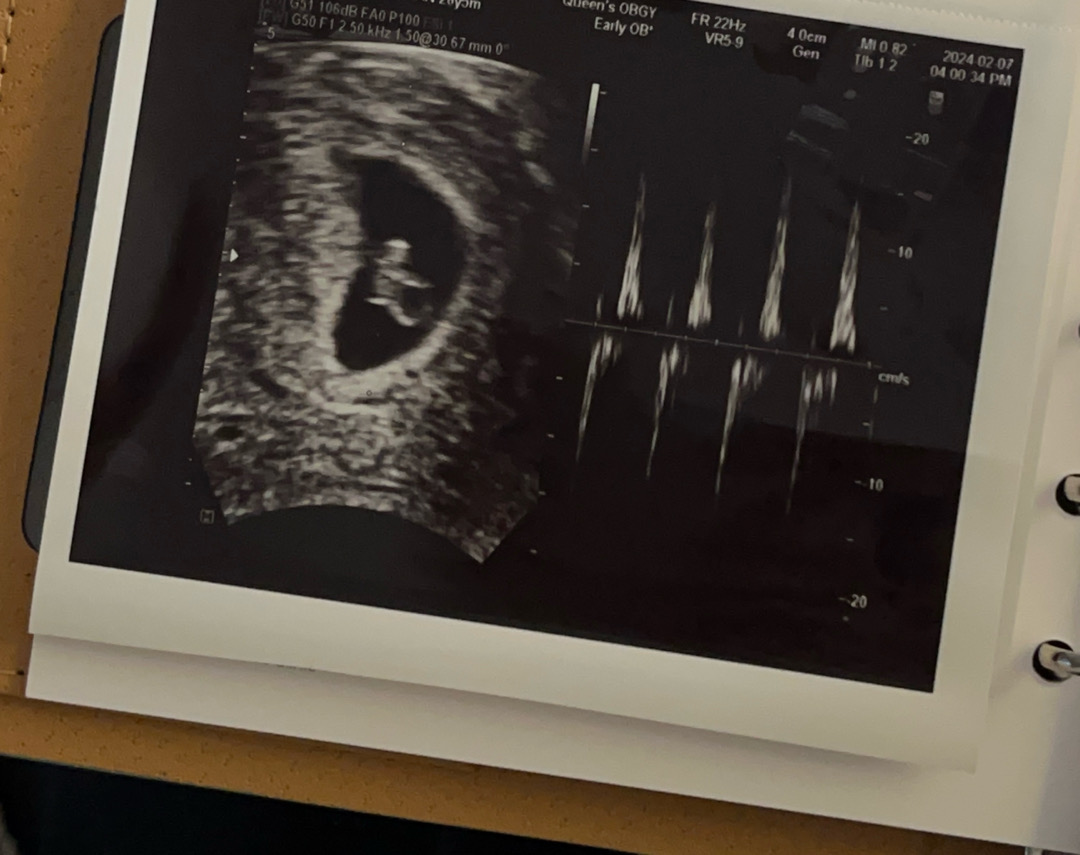

안녕하세요 오늘로 6주 5일차 심소 듣고왔어요 >_< 남편 퇴근시간때문에 혼자 다녀왔는데 하필 오늘 기계가 고장나서 녹화가 안됐다네요 😭 ㅠㅠㅠ 들려주려고 했는데 ㅠㅠㅠ 제가 직접 듣기엔 우렁찬거같은데 원장님께서 따로 심박수도 말씀안해주시고 저도 까먹고 못 여쭤봐서 ㅠㅡㅠ 사진 보니까 심장박동?도 같이 나와있더라구요 혹시 이 사진으로 보시기엔 심장박동 괜찮아 보이나요?!?!